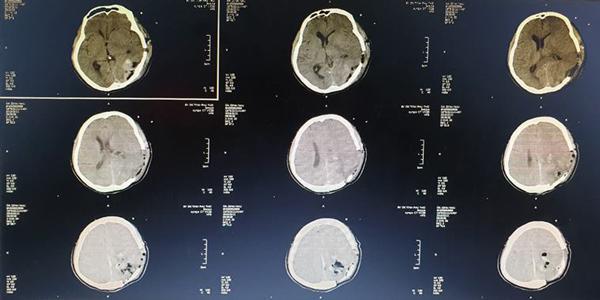

Ổ sán trong não bệnh nhân được lấy ra ngoài.

Cuộc phẫu thuật kéo dài khoảng 2 giờ, ổ sán trong não đã được kíp phẫu thuật sử dụng các trang thiết bị hiện đại như kính hiển vi phẫu thuật, máy hút siêu âm cùng với kinh nghiệm chuyên môn đã lấy được chọn vẹn cả ổ nang sán. Sau mổ 10 ngày, bệnh nhân đã hồi phục, tỉnh táo, không liệt, đi lại và sinh hoạt bình thường.